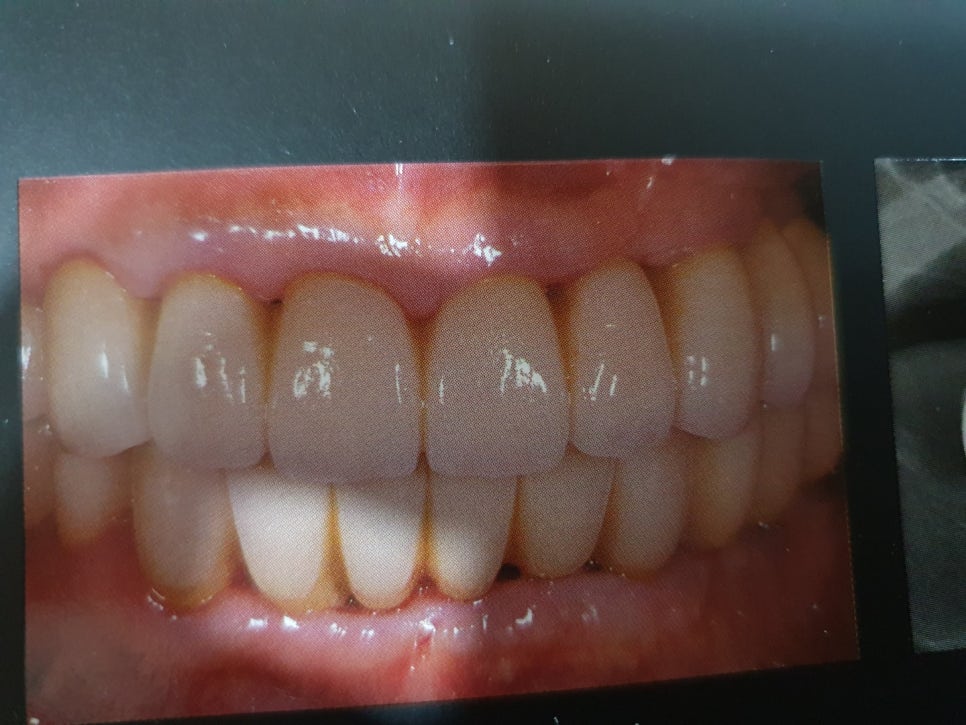

앞니등많은 갯수를 임플란트하여완성한

모습입니다.